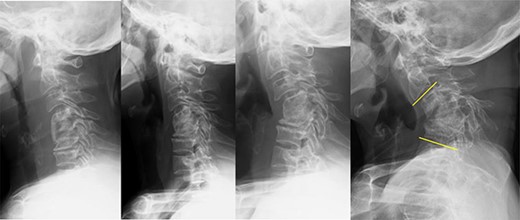

In the second stage, bilateral resection of the fused C3/4, 4/5 and 5/6 facet joints and C3–5 laminae was performed, followed by corrective fixation of C2-T1 (C2, C7 and T1 pedicle screws and C3 and C4 lateral mass screws were placed and corrected with lordotic rod). The C2–7 angle was corrected from −65° to −6°. In the third stage, an autologous fibula was grafted into the space created after resection (Fig. 4).

Radiography image after the three-stage combined surgery; cervical alignment was improved after this approach (the C2–7 angle was corrected from −65° to −6°).